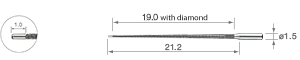

• Diamant-Beschichtung

• für Wurzelkanalerweiterung 23 mm

• Packung à 3 St.

• Diamant-Beschichtung

• für Wurzelkanalerweiterung 26 mm

• Packung à 3 St.

• Diamant-Beschichtung

• für Wurzelkanalerweiterung 32 mm

• Packung à 3 St.